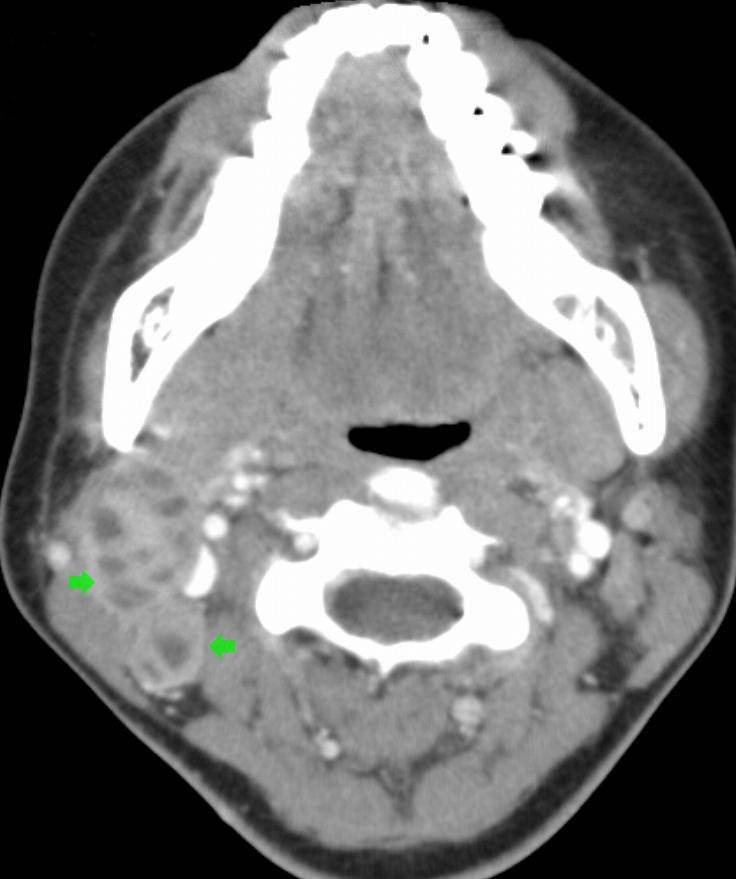

| Снимок шейного лимфаденита |

- магнитно – резонансной и/или компьютерной и томографии;

- компьютерную томографию для визуализации очага заболевания и окружающих тканей;